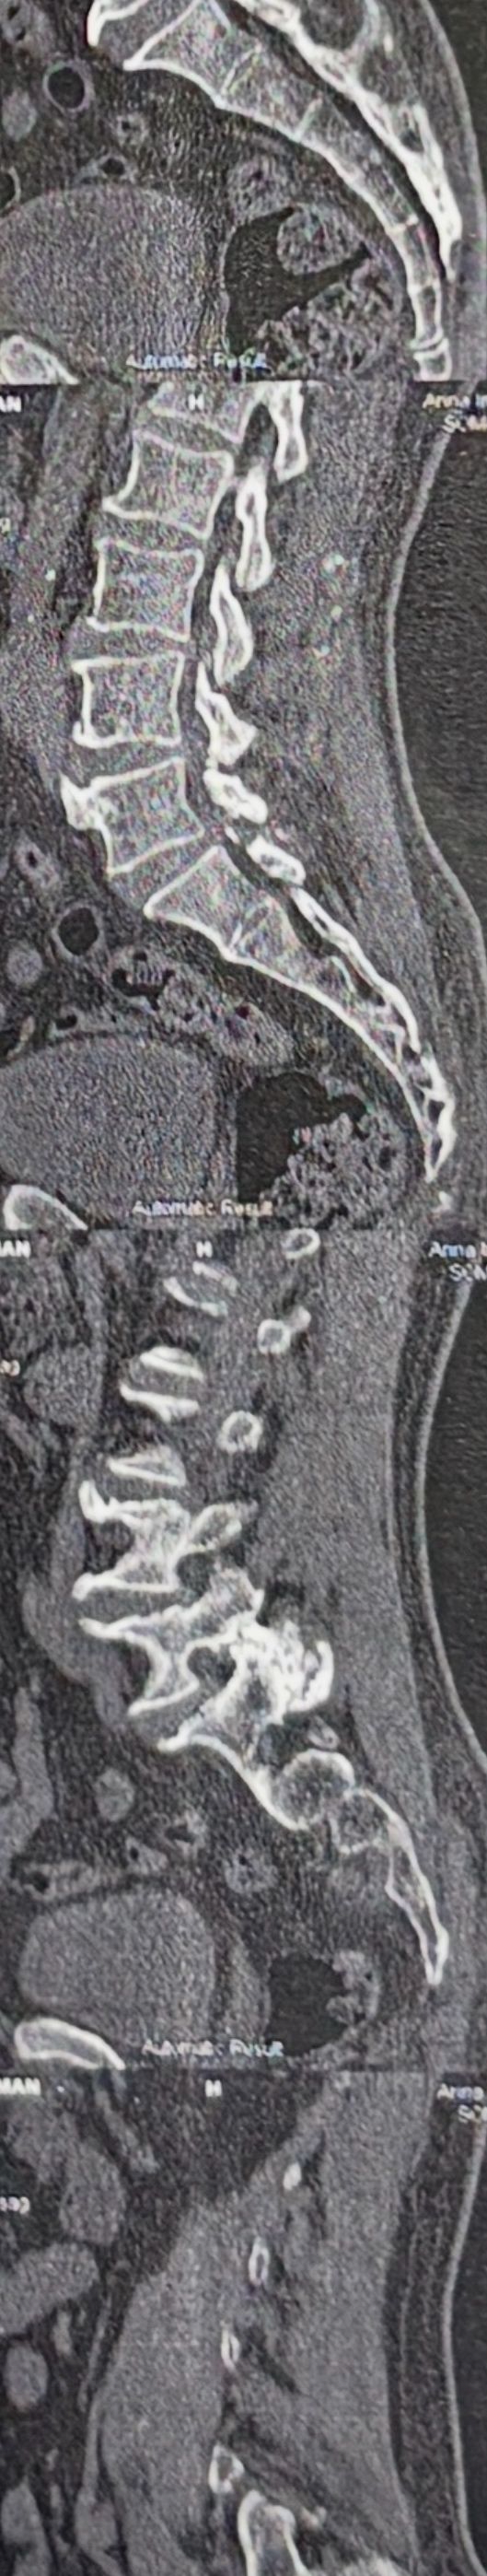

Few weeks ago I posted a case with an old TB spondylitis and listhesis with old fractures and severe canal stenosis (in her lower lumbar). A neurosurgeon who works with us at my clinic saw her in the second session

I attached her CT scan. Her PPD which was positive 2 months ago now it’s less than 3 mm. Since this patient has just low back pain and no radicular pain and can walk easily our neurosurgeon suggested no surgery and we emphasized that she has to complete her medication and be under her infectious diseases specialist

And if other signs and symptoms develops have to see surgeon again

42 years old female presented to my clinic yesterday on May15/2025 with chronic Low back for 2 yrs. She is from afghanestan and arrived to tehran 3 month ago. Visited pain specialist 3 months ago who just did PPD test and gave her Anti TB medication. In examination just had severe focal khyphosis from L3 to L5 without any tenderness. Her mri was done 2 months ago. Report is in Farsi and mentions of paraspinal puss/ fluid collection esp in psoas muscles, with extension of fluid collection to R pelvic region. Had 2 site of severe canal stenosis due to previous fractures of L3,4,5 and movement of fractured bones to the canal with complete distractions of those levels discs with fusion of L3 to L5

I ordered C T scan of lumbar and pelvic MRI / chest x r and reffered her to neurosurgon and infectious disease specialist to get full assessment and possible hospitalized for biopsy and surgery

As you know doctors of chiropractic would never. give treatment to patients with spinal Discitis/ osteomyelitis/ metastasis/ fracture( absolute chiropractic contraindications for treatment)